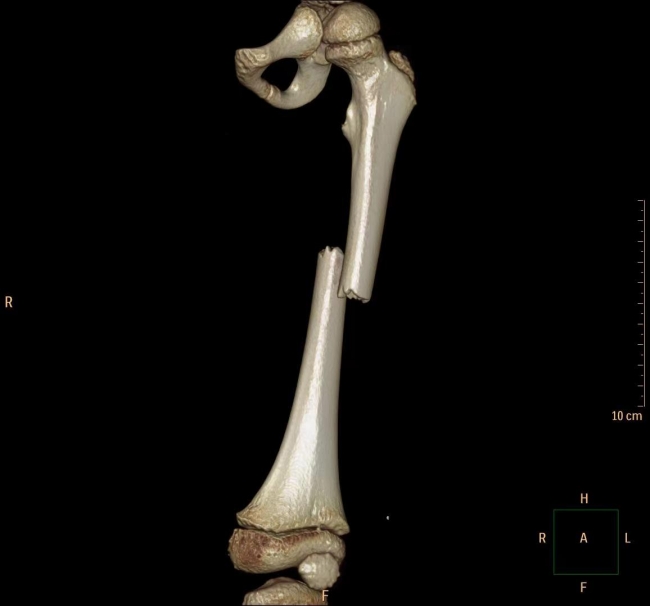

今年五岁的小男孩乐乐(化名),在家中阳台上玩耍时,不慎从二楼(约7米高处)摔下,致左大腿疼痛、畸形、活动障碍,家长立即送他到当地医院救治。X片检查提示,乐乐左侧股骨中段短斜型骨折,骨折断端成角重叠移位,患肢短缩明显,建议转上级医院行手术治疗。